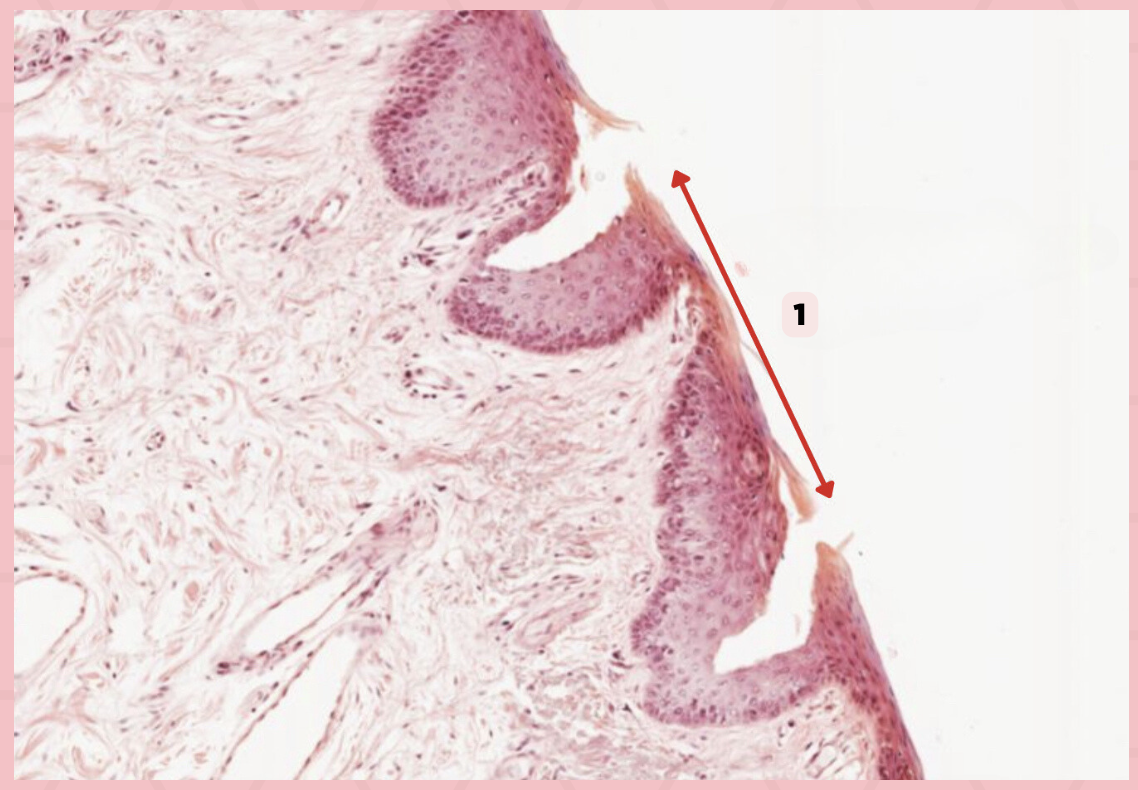

a. Abrupt Transition from keratinized to nonkeratinized epithelium

Identify the structure’s lining epithelium given in the image?

a. Abrupt Transition from keratinized to nonkeratinized epithelium

b. Abrupt Transition from nonkeratinized to keratinized epithelium

c. AOTA

d. NOTA

Lip

What specimen is being showed in the picture?

Mucocutaneous Junction

Identify the structure labeled as 1.